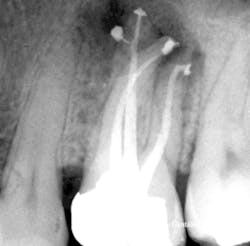

In 1989, I conceived of a way to radically simplify 3-D obturation.This new method collapsed Schilder's Vertical Condensation Technique of three-to-five heating and packing steps requiring five minutes per canal, into a downpack that required just two procedural steps and less than 15 seconds per canal to complete. While it was my intention was to simplify Schilder's procedure, the surprise result was a "centered" condensation technique that, despite the huge reduction in time and skills needed, actually provided superior obturation results that moved more gutta-percha into lateral complexities than vertical condensation (figures 2, 3, 4a, and 4b). (2)

Figure 4a: Sagittal dissection of the mesial root of an extracted mandibular molar, showing 3-D obturation result with the Continuous Wave of Obturation Technique. Note the gutta-percha and sealer completely filling the isthmus between the MB and ML canals. (Courtesy of Robert Sharp, DDS)

Figure 4b: Sagittal dissection of MB root of an extracted maxillary molar, showing a similar 3-D obturation result with the Continuous Wave of Obturation Technique. Note the gutta-percha and sealer completely filling the isthmus between the MB1 and MB2 canals. (Courtesy of Gary Carr, DDS)